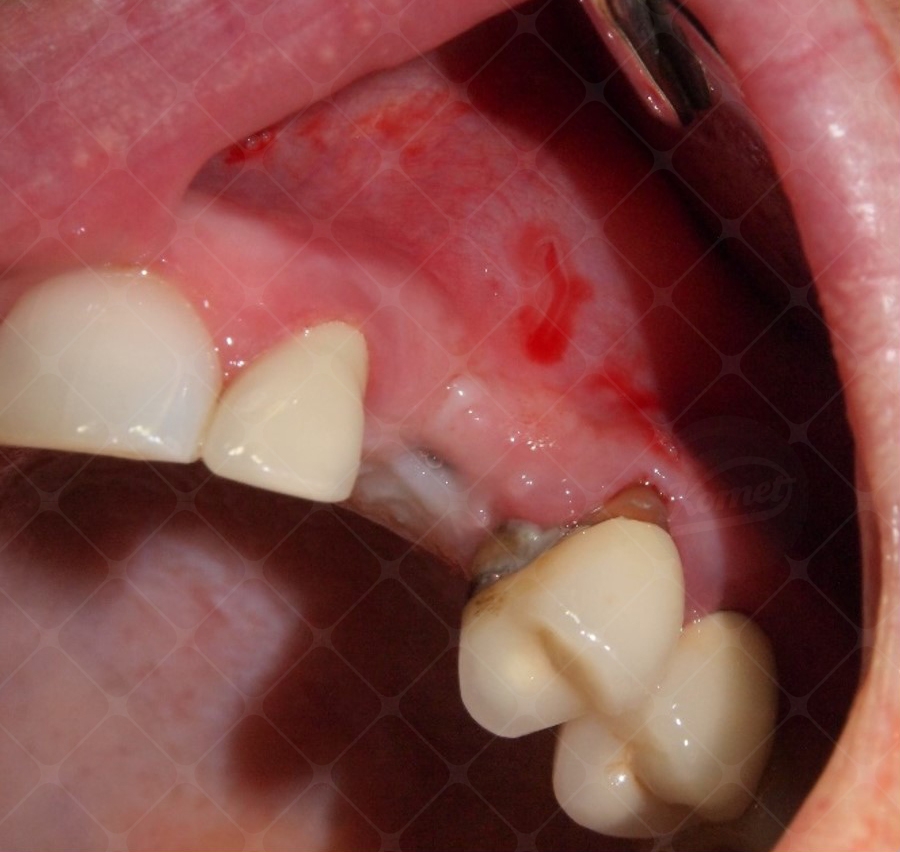

Una paziente di 48 anni femmina giunge all'osservazione per una frattura dell’elemento 2.3.

All’EO intraorale è visibile il residuo radicolare di 2.3. L’elemento dentario era stato precedentemente trattato endodonticamente ed ospitava un perno endocanalare.

L’esecuzione di un esame radiografico endorale digitale dimostra la presenza di una frattura verticale radicolare. L’esecuzione di una misurazione radiografica consente di stimare una quota ossea post-estrattiva disponibile pari a 13 mm. La biodisponibilità è adeguata all'eventuale posizionamento implantare post-estrattivo di una fixture di 11.5 mm di lunghezza. Viene eseguita l’anestesia locale per infiltrazione con mepivacaina cloridrato al 2% associata ad adrenalina in concentrazione 1:100000.